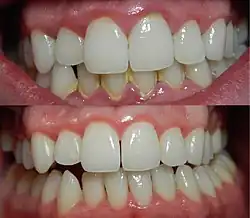

![]() | |

| A severe case of gingivitis | |

.jpg)

Additionally, the stippling that normally exists in the gum tissue of some individuals will often disappear, and the gums may appear shiny when the gum tissue becomes swollen and stretched over the inflamed underlying connective tissue. The accumulation may also emit an unpleasant odor. When the gingiva are swollen, the epithelial lining of the gingival crevice becomes ulcerated and the gums will bleed more easily with even gentle brushing, and especially when flossing.